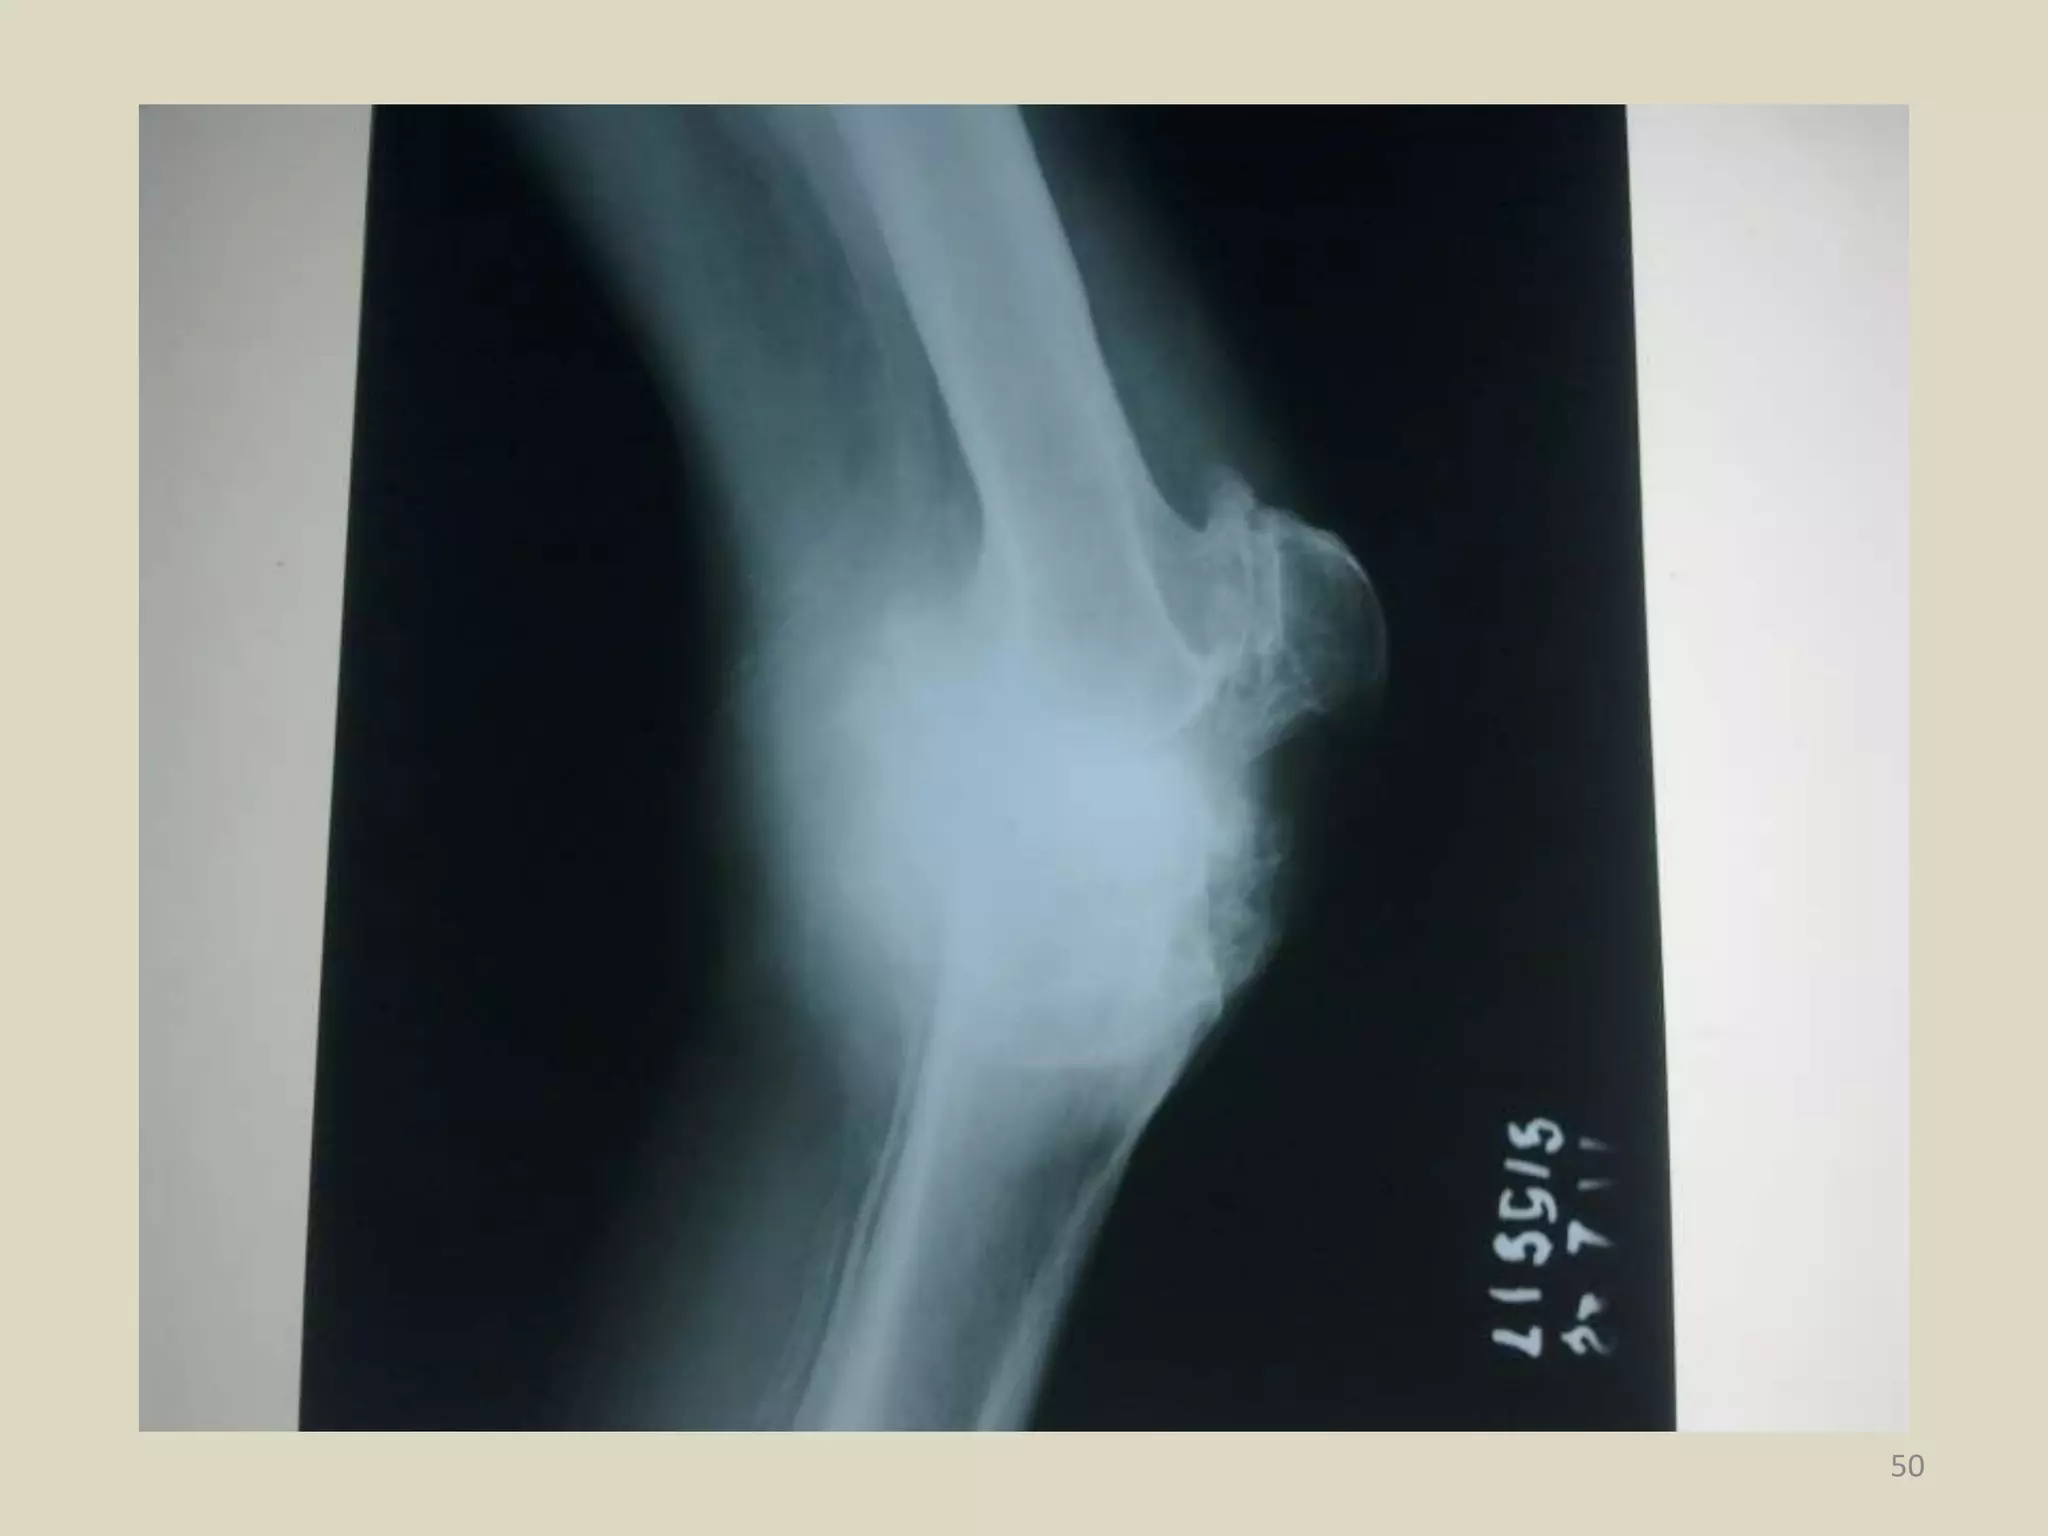

Radiographic appearance

Radiographic Criteria

 Loss of joint space

 Sub-chondral sclerosis or cyst formation

 Presence of new bone formation or

osteophytes

Radiographic appearance Radiographic Criteria Loss of joint space  Sub-chondral sclerosis or cyst formation  Presence of new bone formation or osteophytes 8